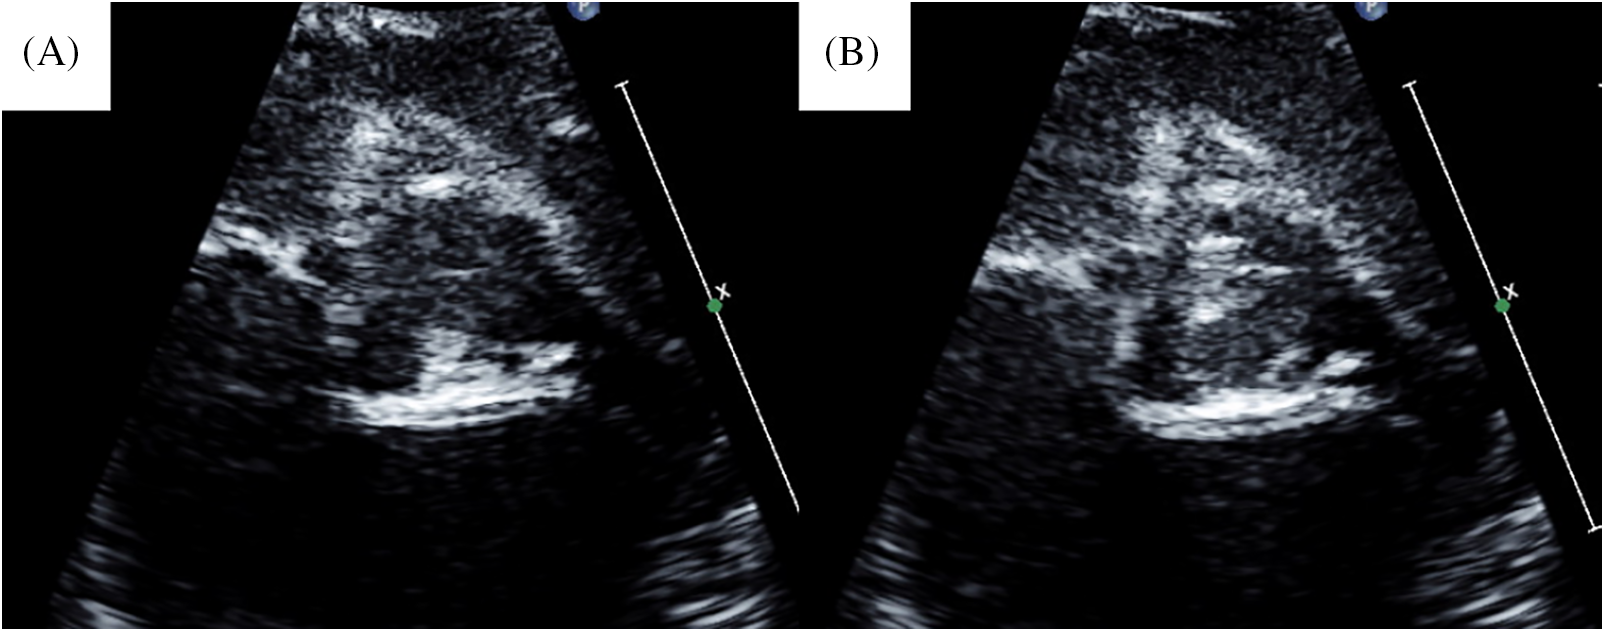

A male neonate, weighing 2.18 kg, delivered spontaneously at 38 weeks was diagnosed with cAS immediately following birth. BVP was performed at 2 days, which led to a slight improvement in cAS. However, AR became severe, and acute heart failure developed. Thus, urgent surgery was planned. Transthoracic echocardiography revealed that his aortic annular diameter was 6.4 mm (103% of the normal annular diameter, Z score = 0.34) with an unicuspid aortic valve (Figs. 1A and 1B). During surgery, the aortic valve was exposed through transverse transection of the aorta 4 mm above the sinotubular junction under cardioplegic arrest. The aortic valve was functionally unicuspid with a well-developed posterior (left−none) commissure and less-developed anterior (left−right) commissure. The aorta was longitudinally incised at the anterior commissure to the ventriculoaortic junction (the open-sleeve technique) [1,2].

Figure 1: Preoperative echocardiogram of case 1. (A) Preoperative image in diastolic phase. (B) Preoperative image in systolic phase